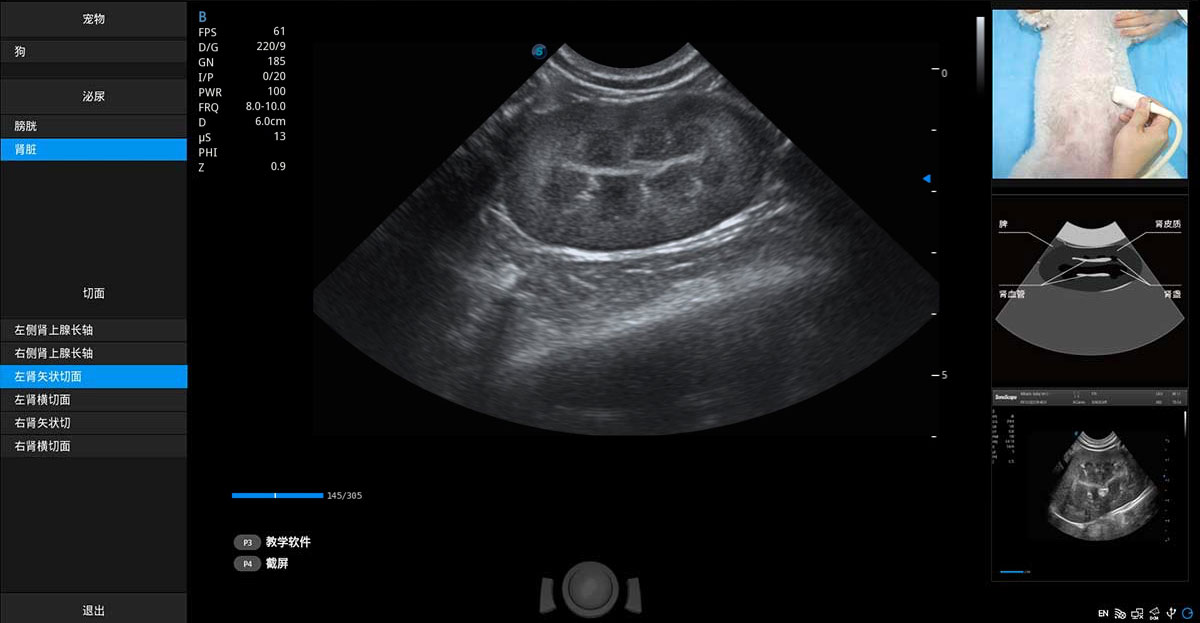

提供解剖示意圖、標(biāo)準(zhǔn)超聲圖像、掃查手法圖和操作者實(shí)時(shí)檢查圖像,指導(dǎo)操作者進(jìn)行標(biāo)準(zhǔn)切面的正確掃查。

ProPet 70專(zhuān)為動(dòng)物醫(yī)生設(shè)計(jì),對(duì)不同的動(dòng)物體型和生理結(jié)構(gòu)作出了針對(duì)性的優(yōu)化。通過(guò)動(dòng)物影像專(zhuān)用軟件,可滿(mǎn)足個(gè)性化的應(yīng)用需求,幫助動(dòng)物醫(yī)生獲得更精確的診斷數(shù)據(jù)。